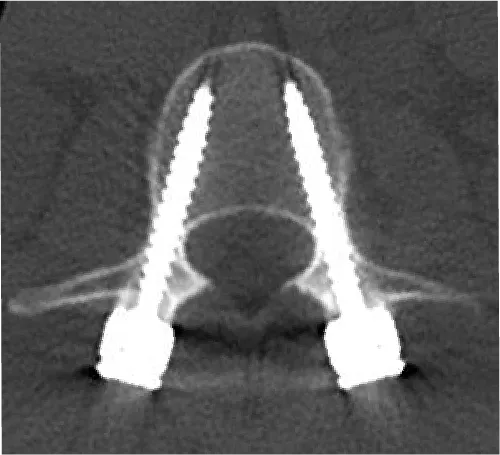

脊椎破裂骨折

交通事故・高所からの転落などの強い外力で背骨が骨折し、変形が強い場合には手術治療が必要になります。

治療法:骨折した椎骨の上下の椎骨に経皮的にスクリューを挿入し、変形を矯正します。さらに骨折した椎骨に人工骨を充填し、骨折部を安定させます。手術翌日から歩行が可能となり、入院期間は1〜2週間程度です。骨折部が治癒した後にスクリューなどは抜去します。

胸椎破裂骨折に対する経皮的内固定術

-

骨折部は人工骨を充填して整復